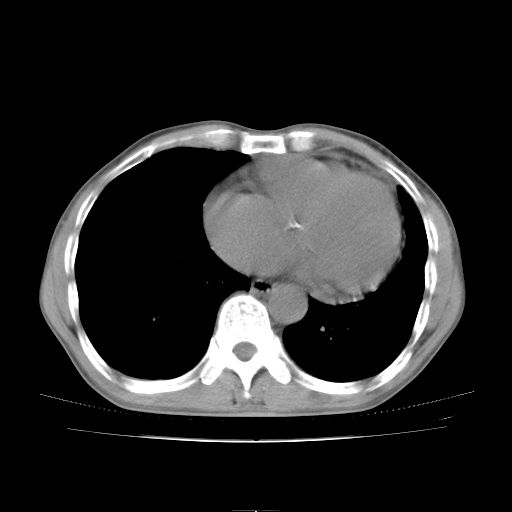

标题: CT25795:感冒后反复咳嗽两月余,痰中带血半月余。X诊断“肺 [打印本页]

标题: CT25795:感冒后反复咳嗽两月余,痰中带血半月余。X诊断“肺

1.双肺肺梗塞(理由:病灶呈三角形,与胸膜相连且局部胸膜肥厚,左心室增大)伴肺感染。

考虑两肺感染性病变,左肺上叶舌段肿瘤性病变待排;建议抗炎治疗后复查。